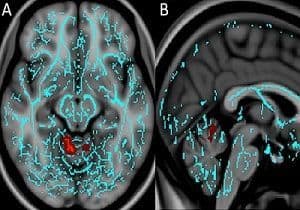

Top image. A, Axial and B, sagittal images derived from tract-based spatial statistics (TBSS) results and rendered on T1-weighted MR images from the Montreal Neurological Institute atlas indicate that significant white matter differences in patients with mTBI and anxiety involve the cerebellar vermis, the region responsible for fear conditioning. Voxels with significant differences detected with TBSS were thickened by using the TBSS fill function into local tracts (red) and overlaid on the white matter skeleton (blue).